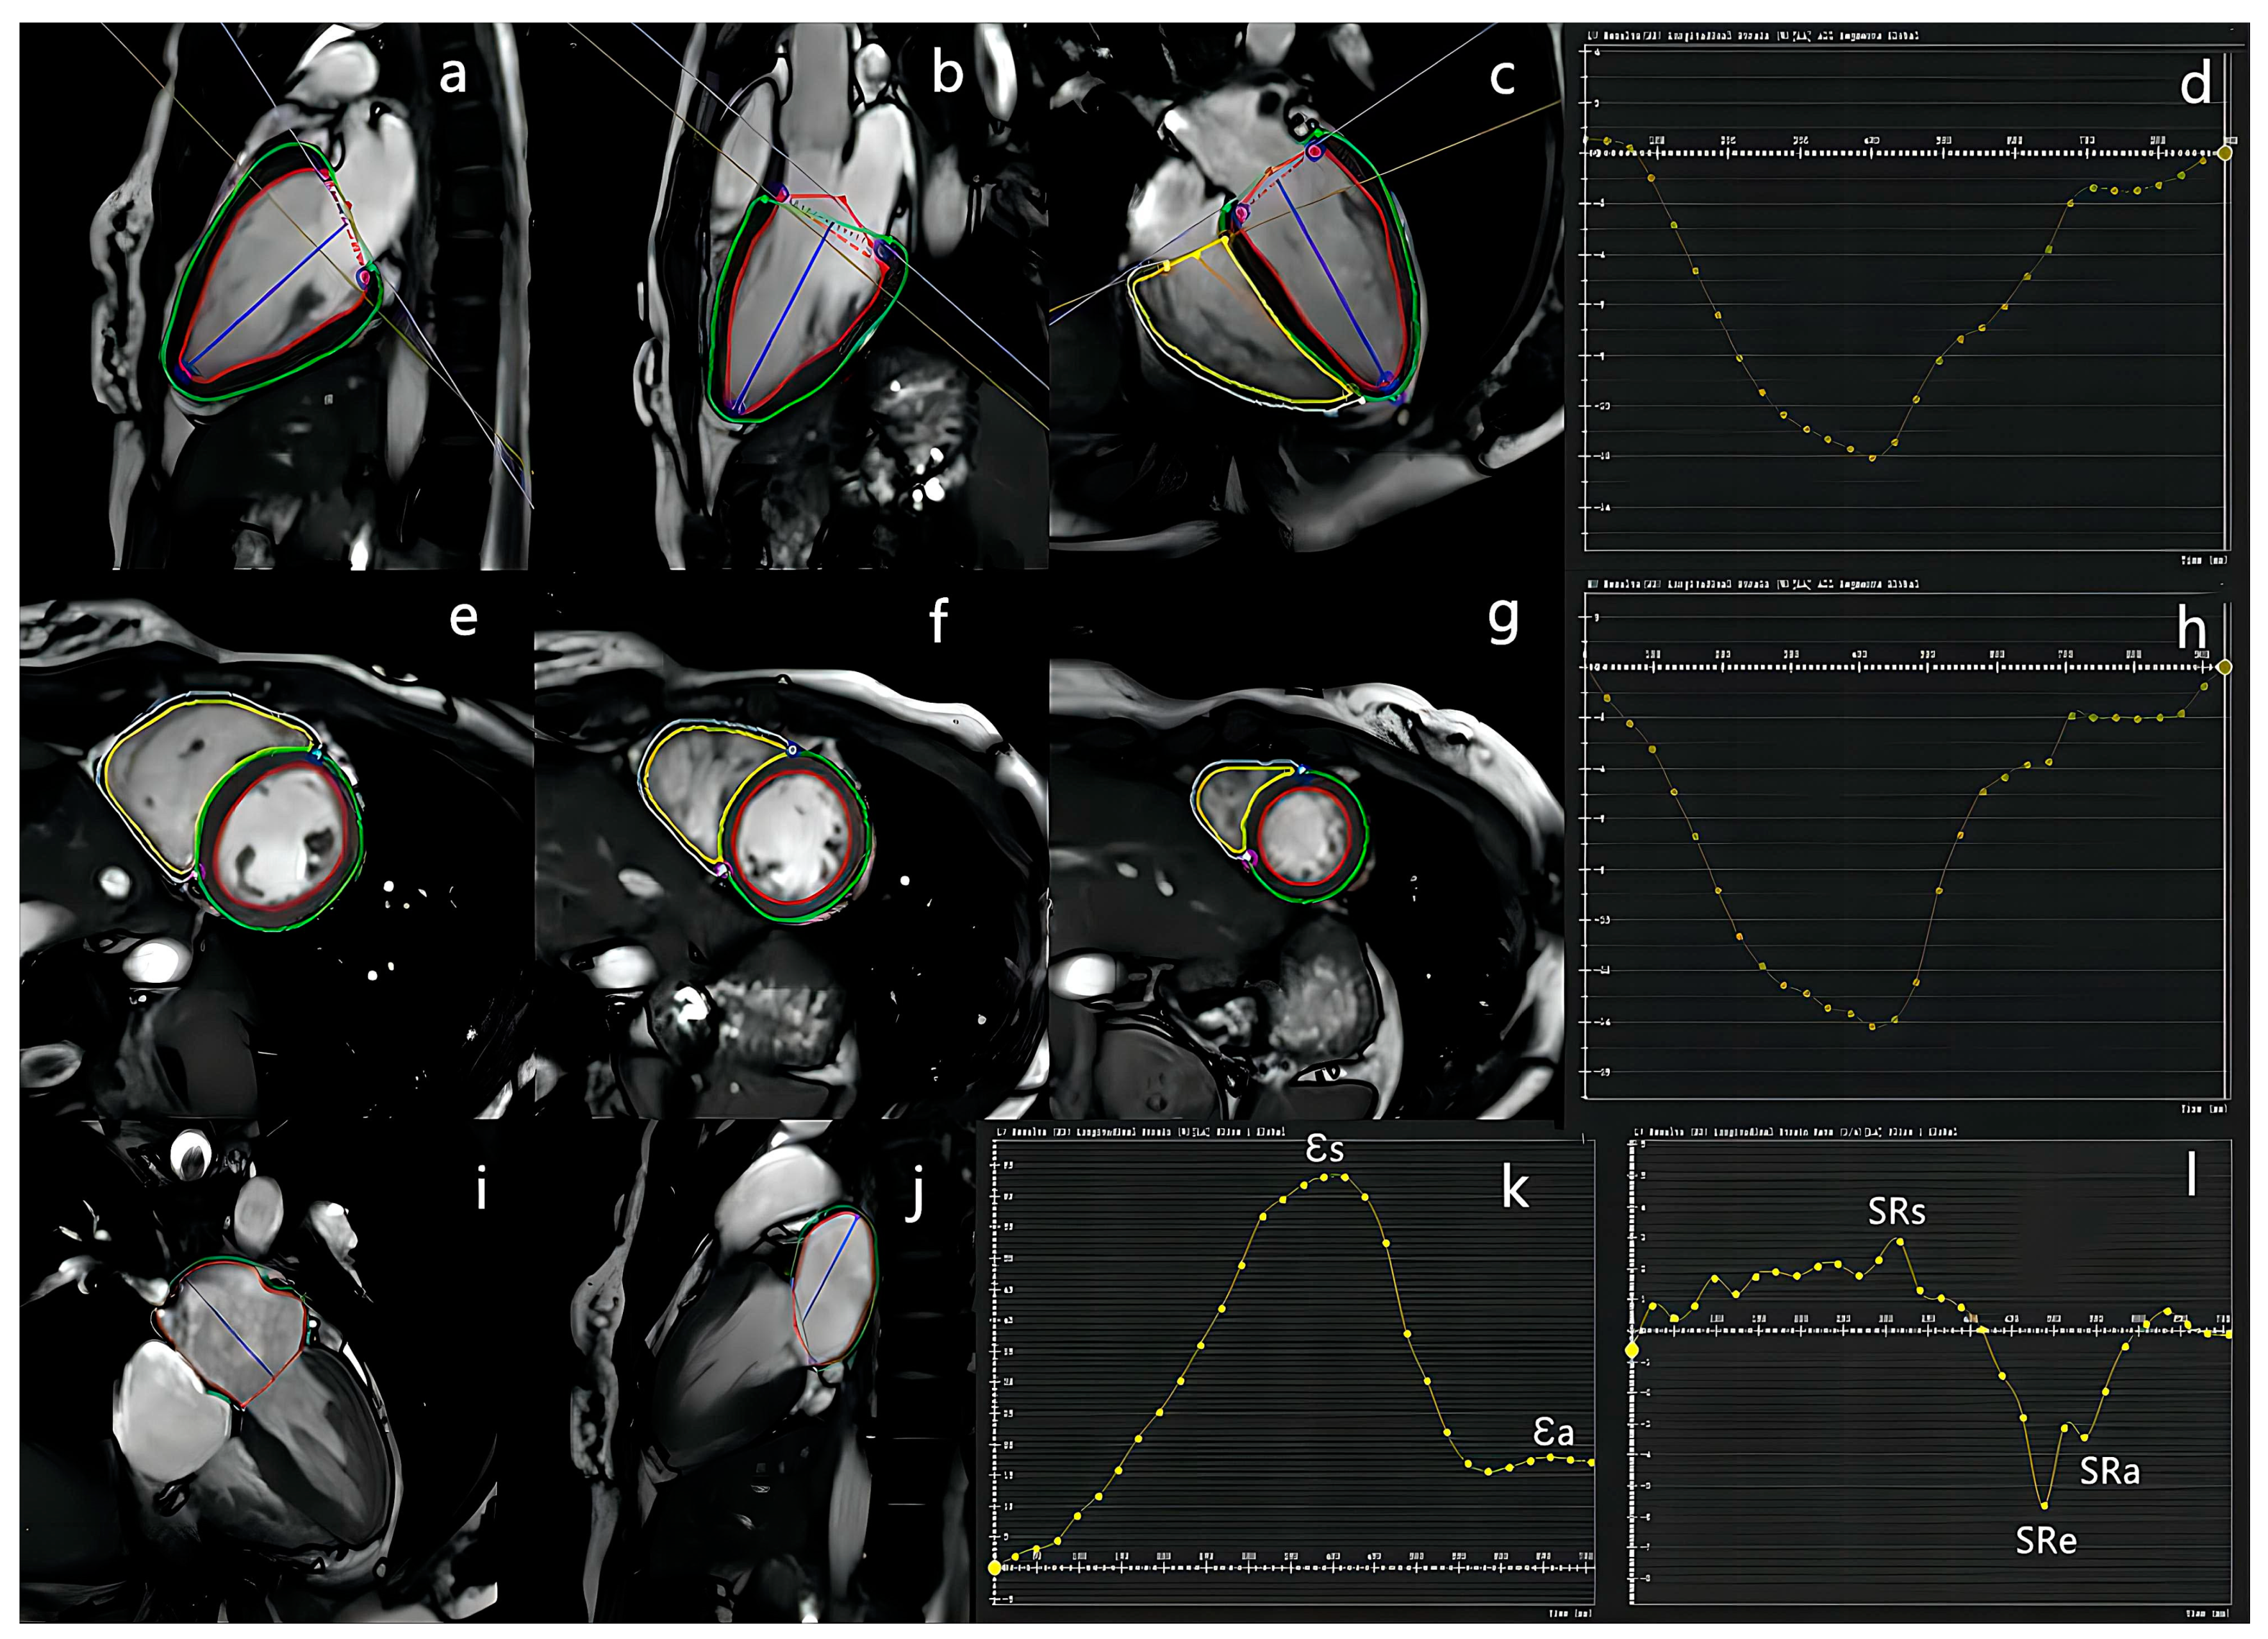

2.3.3. FT Analysis

2.4. Follow-Up